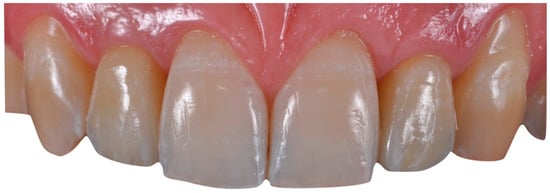

The case describes rehabilitating two congenitally missing lateral incisors in a young patient (38 years old) undergoing orthodontic treatment to create the necessary space for implant placement (Figure 1 and Figure 2). Two fibre-reinforced composite Maryland bridges (Tender Fiber Quattro—Micerium) were utilised for provisional rehabilitation (Figure 3, Figure 4 and Figure 5). Two Osstem TSIII 3.5 × 10.0 implants (1.5 mm subcrestal), two straight Osstem Zirconia abutments, and two-layered lithium disilicate crowns were employed for the definitive restoration (Figure 5, Figure 6, Figure 7, Figure 8, Figure 9, Figure 10, Figure 11, Figure 12, Figure 13, Figure 14, Figure 15, Figure 16, Figure 17, Figure 18, Figure 19 and Figure 20) [,]. The dental implant position was planned after a three-dimensional radiographic analysis in a prosthetically guided way. Patient rehabilitation was performed with an immediate post-surgery provisional (Maryland-type, cemented with a resinous cement) application. Subsequently, a delayed loading of the new provisional dental implant was retained (cemented with zinc oxide eugenol cement) and finally, definitive crowns (cemented with a definitive resinous cement) on Osstem® abutments were installed (3 months).

Figure 17. Mucosal profile (a) and crown placement (b,c) (fabricated with lithium disilicate ceramics (e-max)).

Figure 19. Completed case.